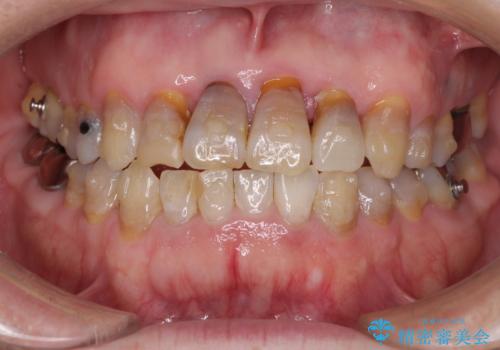

- 前歯の叢生と臼歯のクロスバイトを気にして来院された患者様です。

急速拡大装置による上顎の側方拡大を行い、その後はインビザラインより歯列を改善することとしました。

20代後半以降の男性は上顎骨の側方拡大処置の成功率が低く、今回も骨を拡大することができませんでした。

しかしながら、歯列を側方に拡大することができ、その後はインビザラインにて叢生を解消することができました。